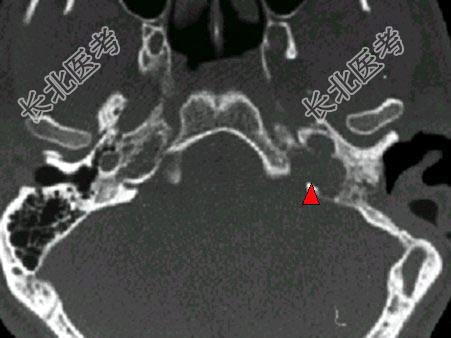

- 单项选择题男,45岁, 左侧搏动性耳鸣半年,耳镜检查透过鼓膜后下部见半膨隆紫红色肿物, CT如图,最可能的诊断是 ( )

E、颈静脉球瘤